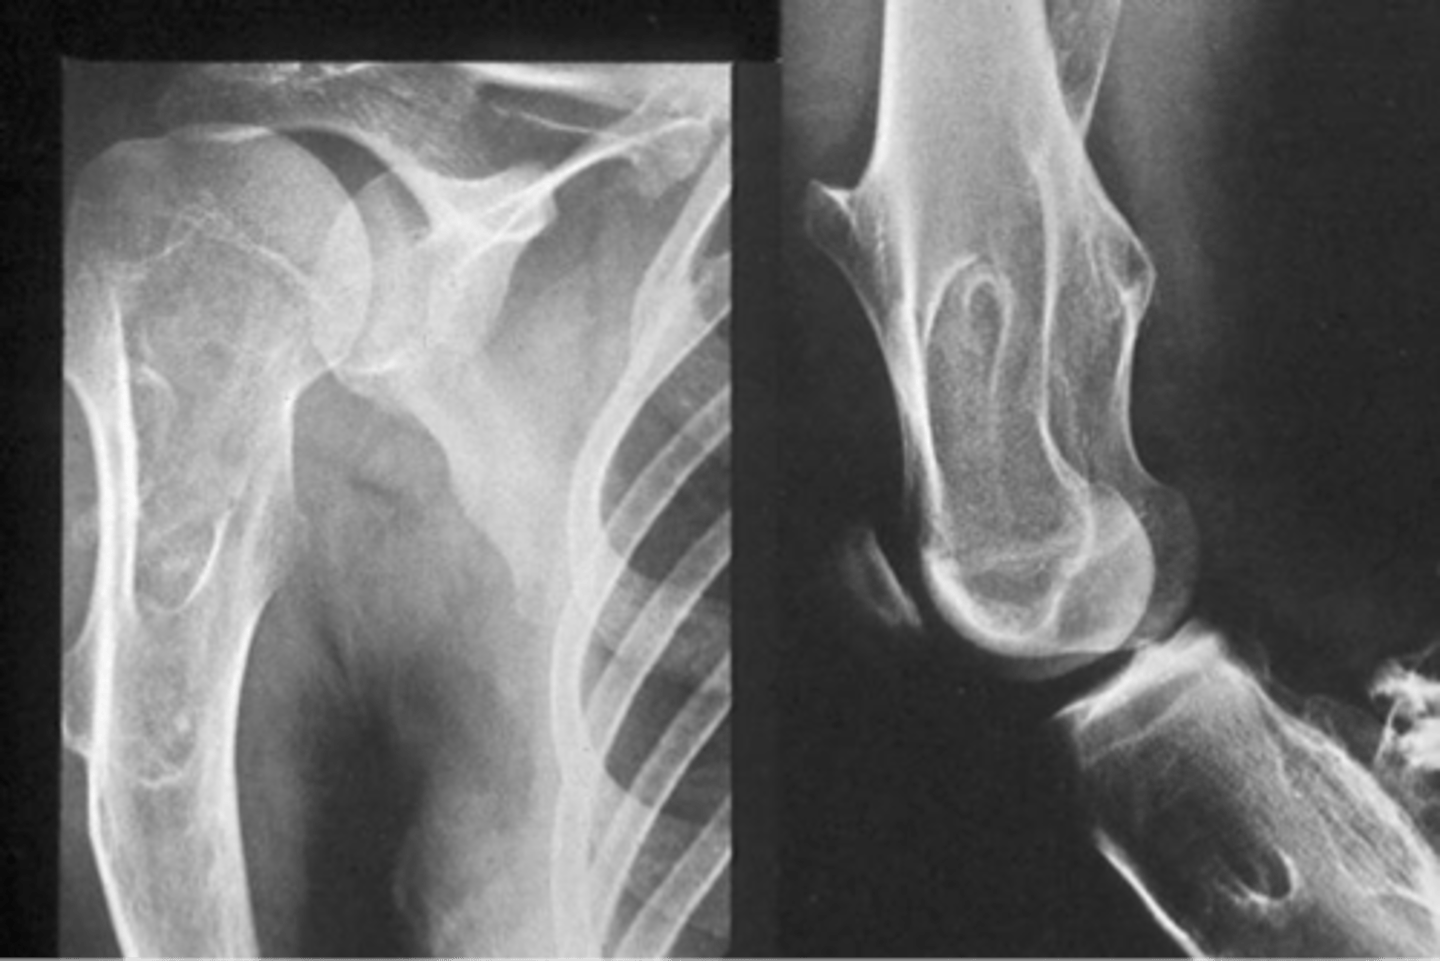

Hereditary multiple exostoses

- Inherited metaphyseal overgrowth

- Multiple painless osteochondromas

- Identical to solitary

- Discovered 2-10 y.o.

- Knee, ankle, shoulder, wrist

<p>- Inherited metaphyseal overgrowth</p><p>- Multiple painless osteochondromas</p><p>- Identical to solitary</p><p>- Discovered 2-10 y.o.</p><p>- Knee, ankle, shoulder, wrist</p>

14

New cards

5-25%

Hereditary multiple exostoses malignant transformation rate

<p>Hereditary multiple exostoses malignant transformation rate</p>